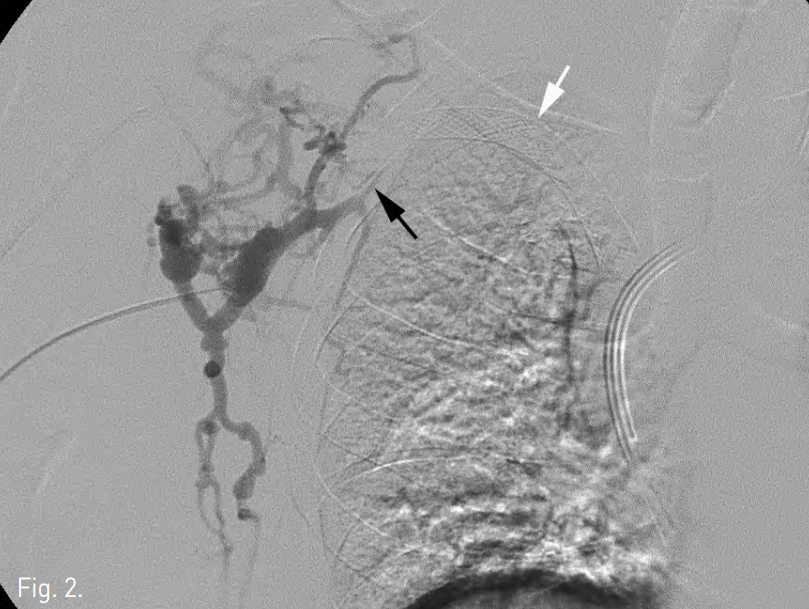

Fig. 2

Venogram shows occlusion of the right subclavian vein (black arrow) with pronounced collateral flow 3 years after placement of a 14 x 60 mm Wallstent (white arrow).